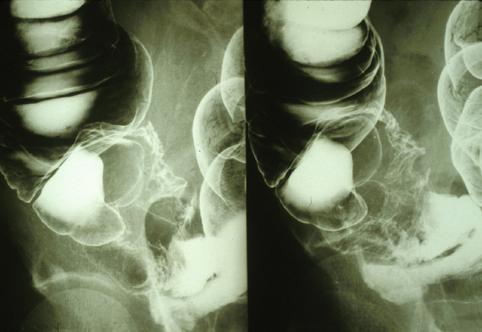

Mucinous cystadenocarcinoma of the appendix (malignant mucocele) in which MRI effectively demonstrated the true nature of the tumor.

Appendix/Mucinous cystadenocarcinoma

Large intestine(Colon)/Appendix

X-ray

40 -